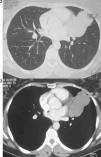

A computed tomography scan (Figs. 2 and 3) revealed a partially cystic heterogeneous mass, forming at the lingular bronchi and then developing in intrathoracic without mediastinal lymphadenopathy or pleural effusion.